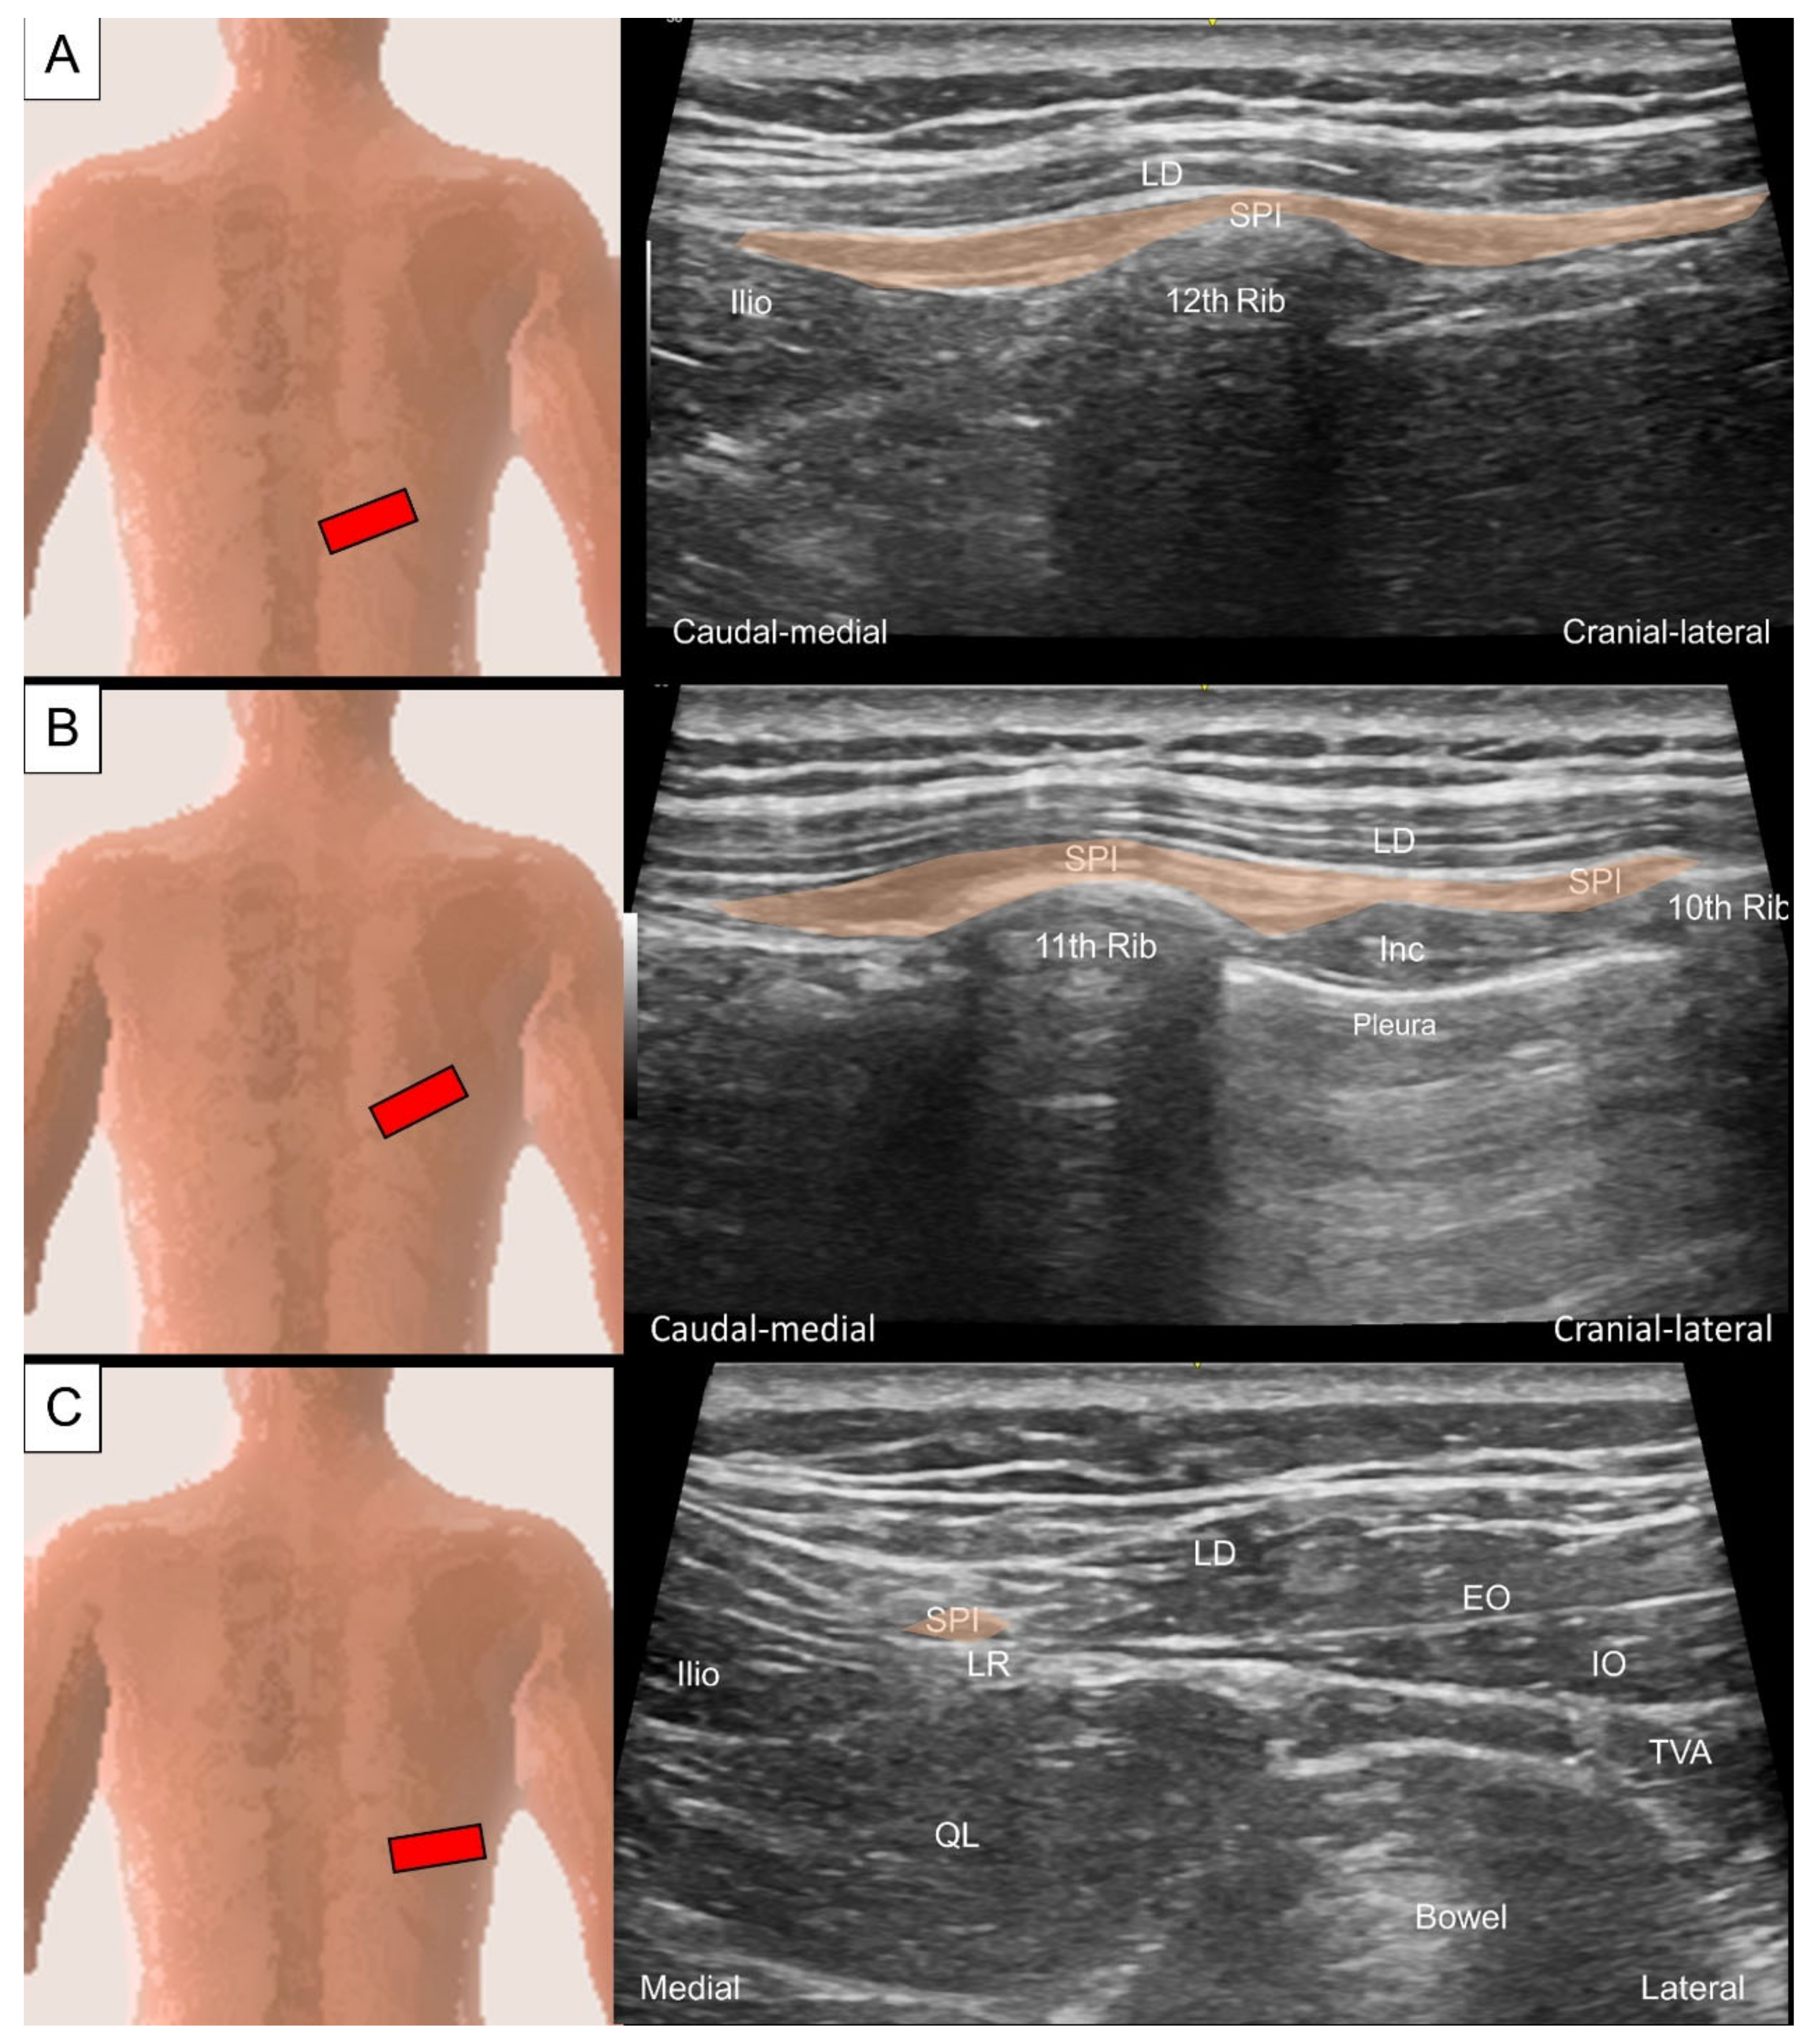

3.1. Serratus Posterior Superior/Inferior

3.1.1. Anatomy

3.1.2. Sonographic Scanning

3.1.3. Clinical Relevance